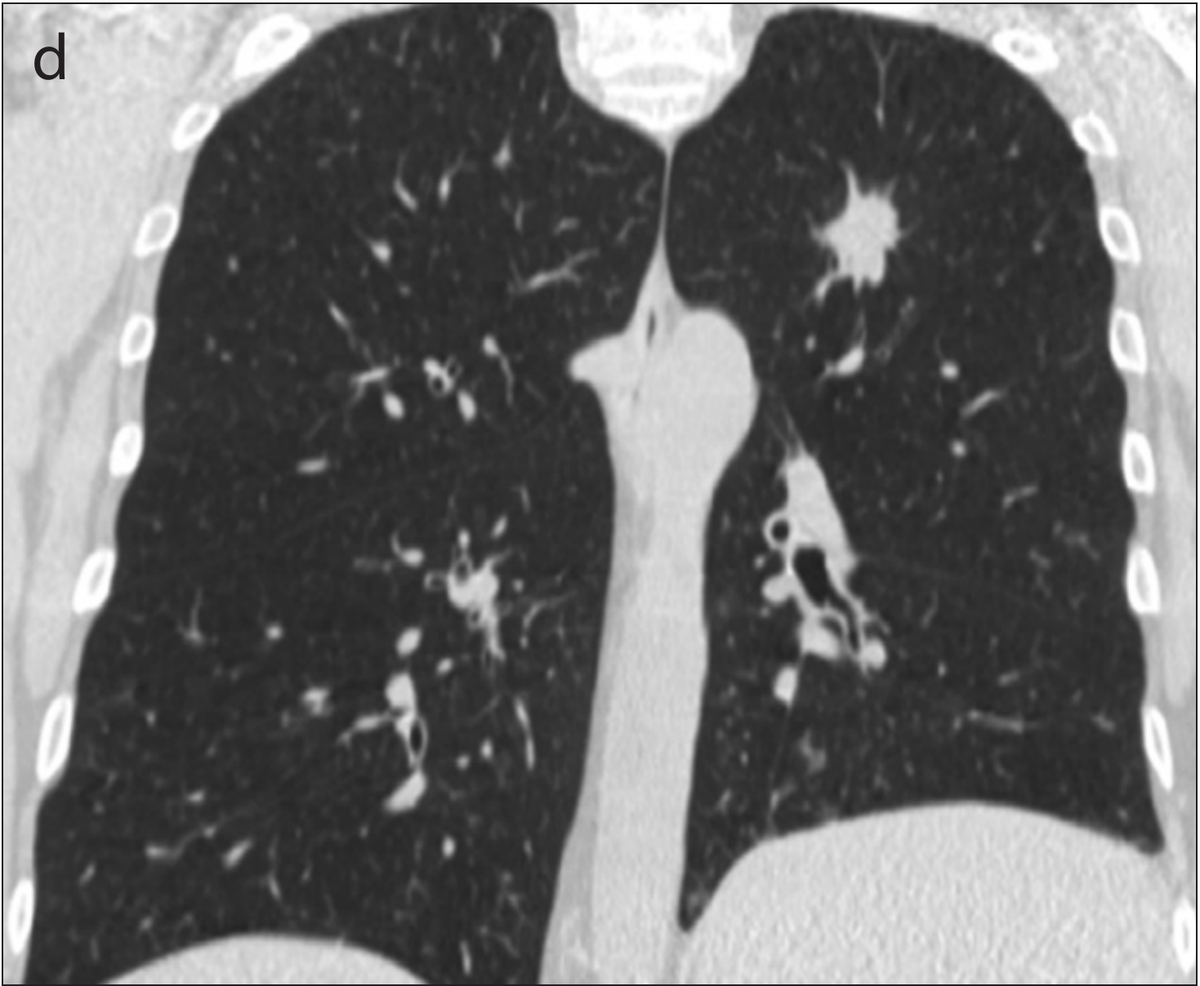

Example 2 shows an example CT scan of a 63-year-old with some of the characteristics described above. The nodule in the scan is small and close to a group of vessels of the upper left lung that partially block it from view, which caused the radiologist reading the scan to miss the tumor. The tumor was detected using a chest x-ray two years later.

Example 2: 63 year old patient with a cancerous lung nodule